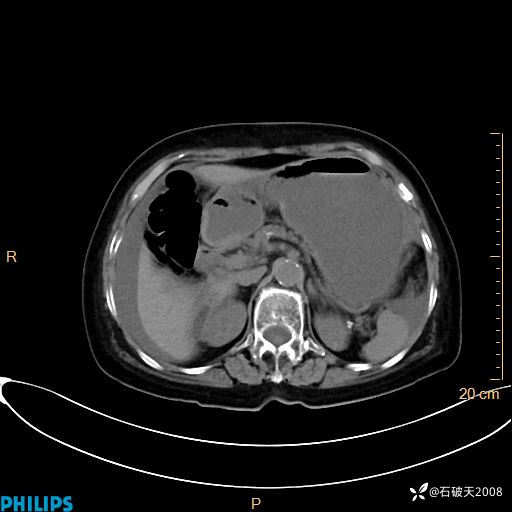

平扫